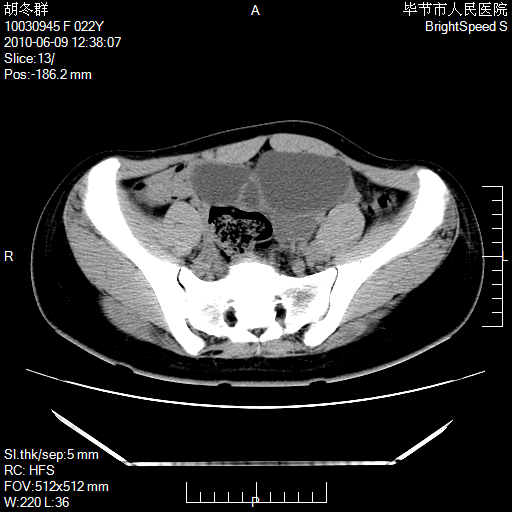

患者23岁,发现腹部包块3月。

盆腔内囊性占位;穿刺或者直接手术拿掉即可,不必紧张。

囊性病变,可以增强检查,不除外输尿管囊肿

盆腔内囊性占位性病变;考虑左侧卵巢囊腺瘤。

有分隔、壁薄,支持考虑左侧卵巢囊腺瘤。

左侧卵巢浆液性囊腺瘤。